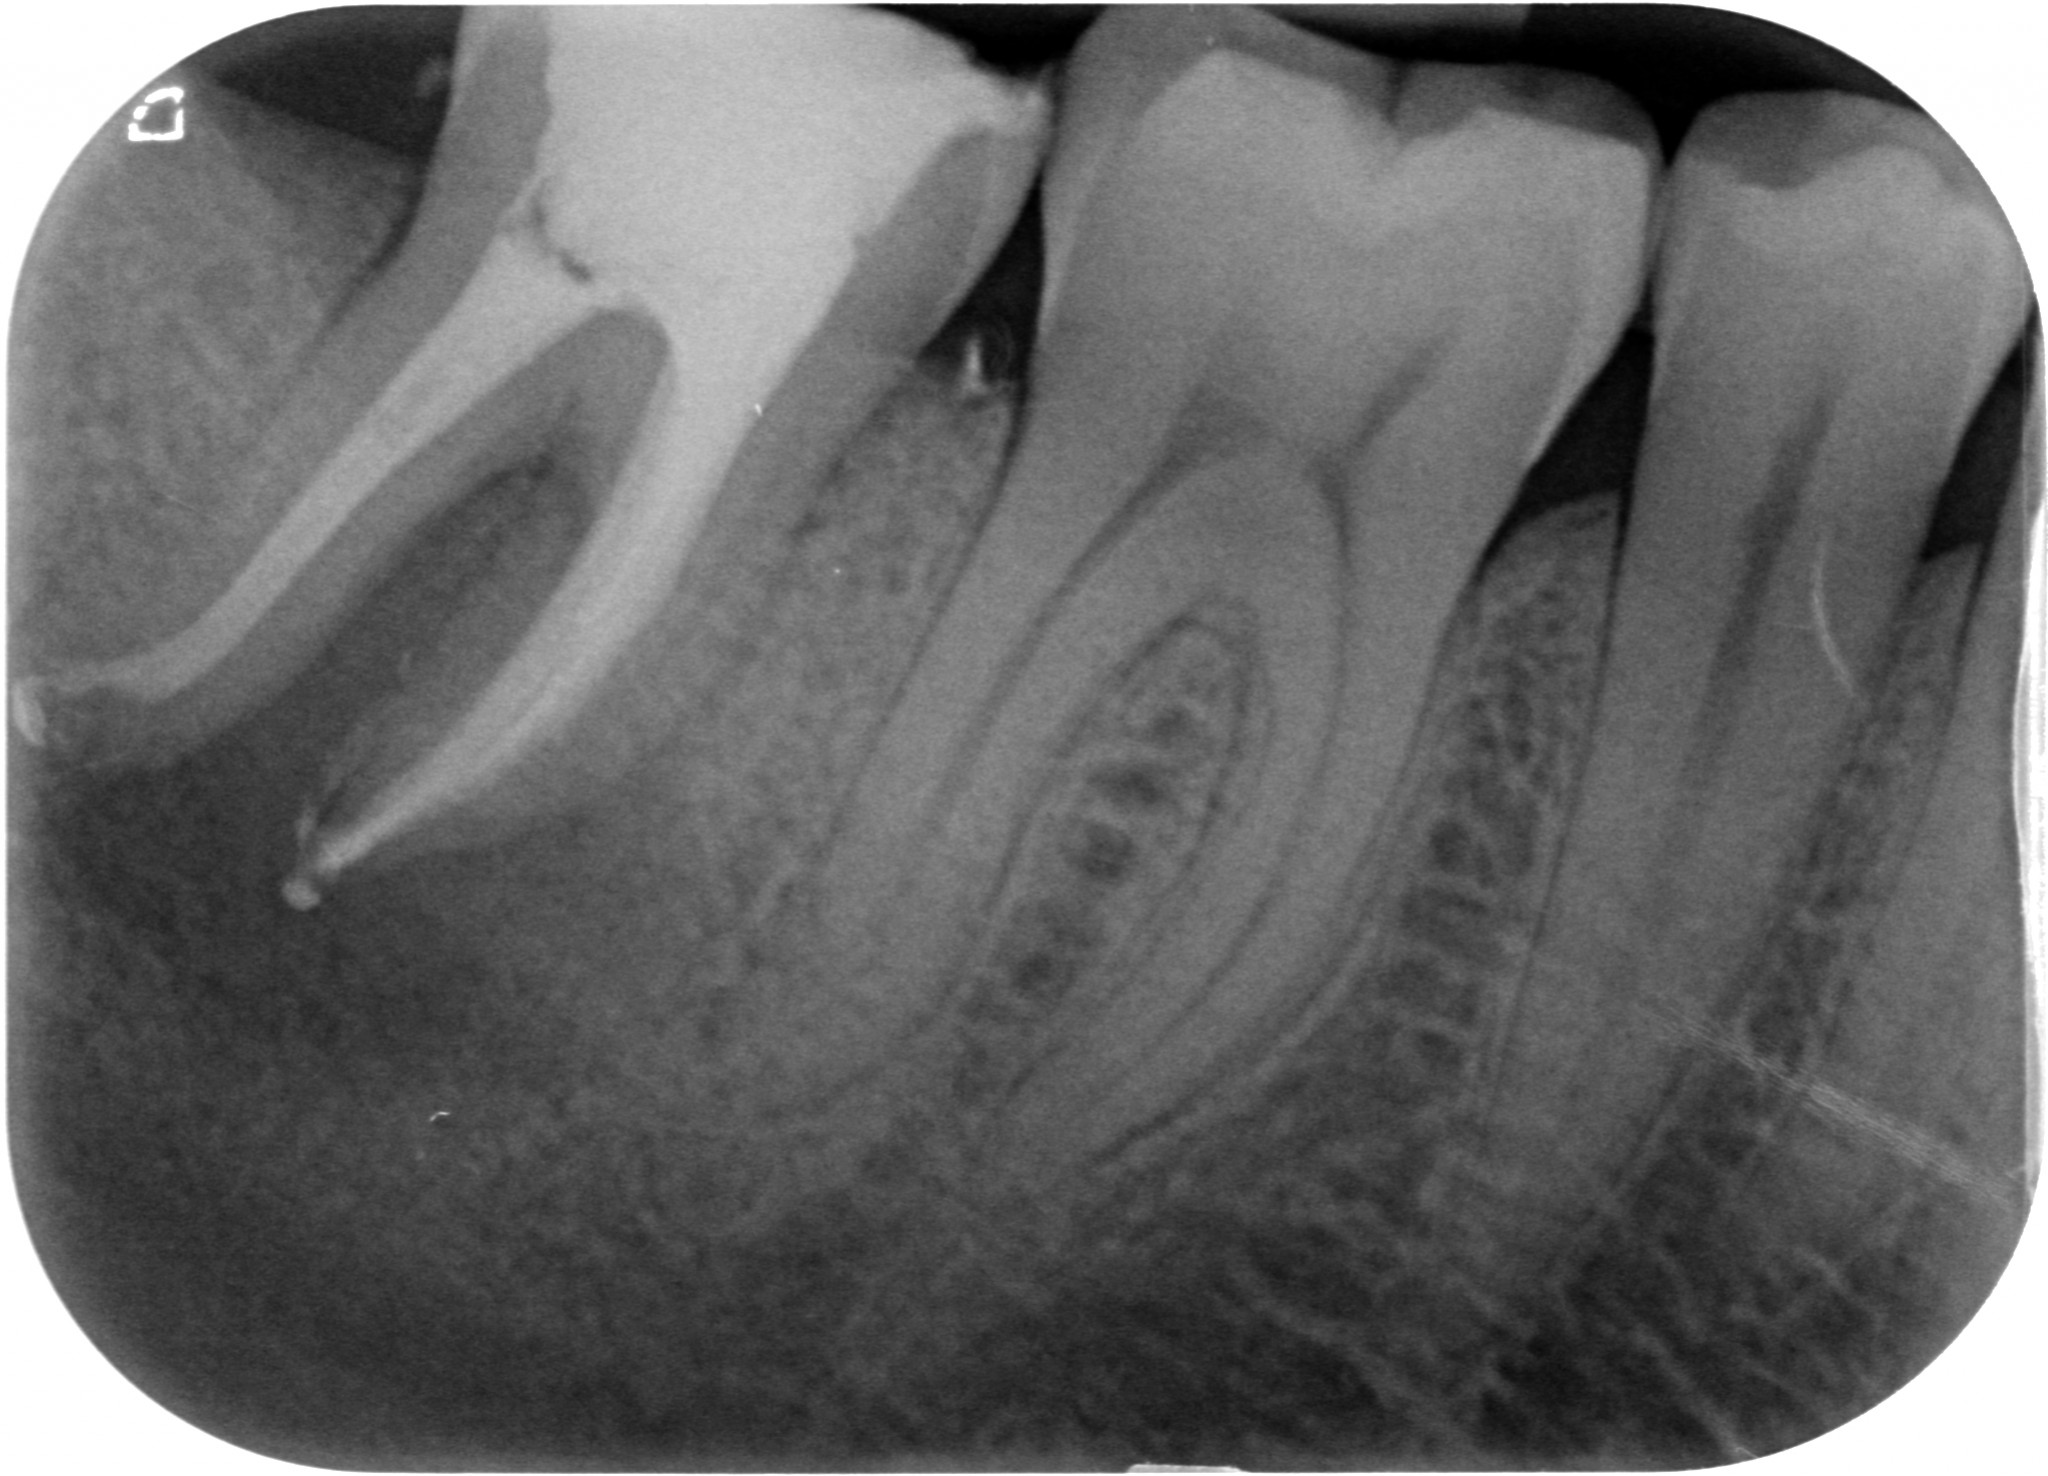

La scoperta che il canale mesiale-mediano deve essere cercato ed è spesso presente ha dato una soluzione a questi casi che mi capitano con una certa frequenza. Canali della radice mesiale del primo molare inferiore chiusi in apparenza bene con lesione. Il mio socio che si occupa quasi solo di chirurgia continuava a dirmi che poteva essere un problema di detersione, ma io a questo non ho mai creduto. Se un canale chiuso radiograficamente bene ha una lesione o è fratturato in verticale o manca un canale.

Canale Mesio-centrale - Radiografie 3.6 iniziale e finaleCanale Mesio-centrale - 3.6 intraoperatoria

In questi casi avverto il paziente delle due ipotesi e appena arrivo a pulire la camera provo subito con impazienza a cercare il canale mancante. E c’è quasi sempre.